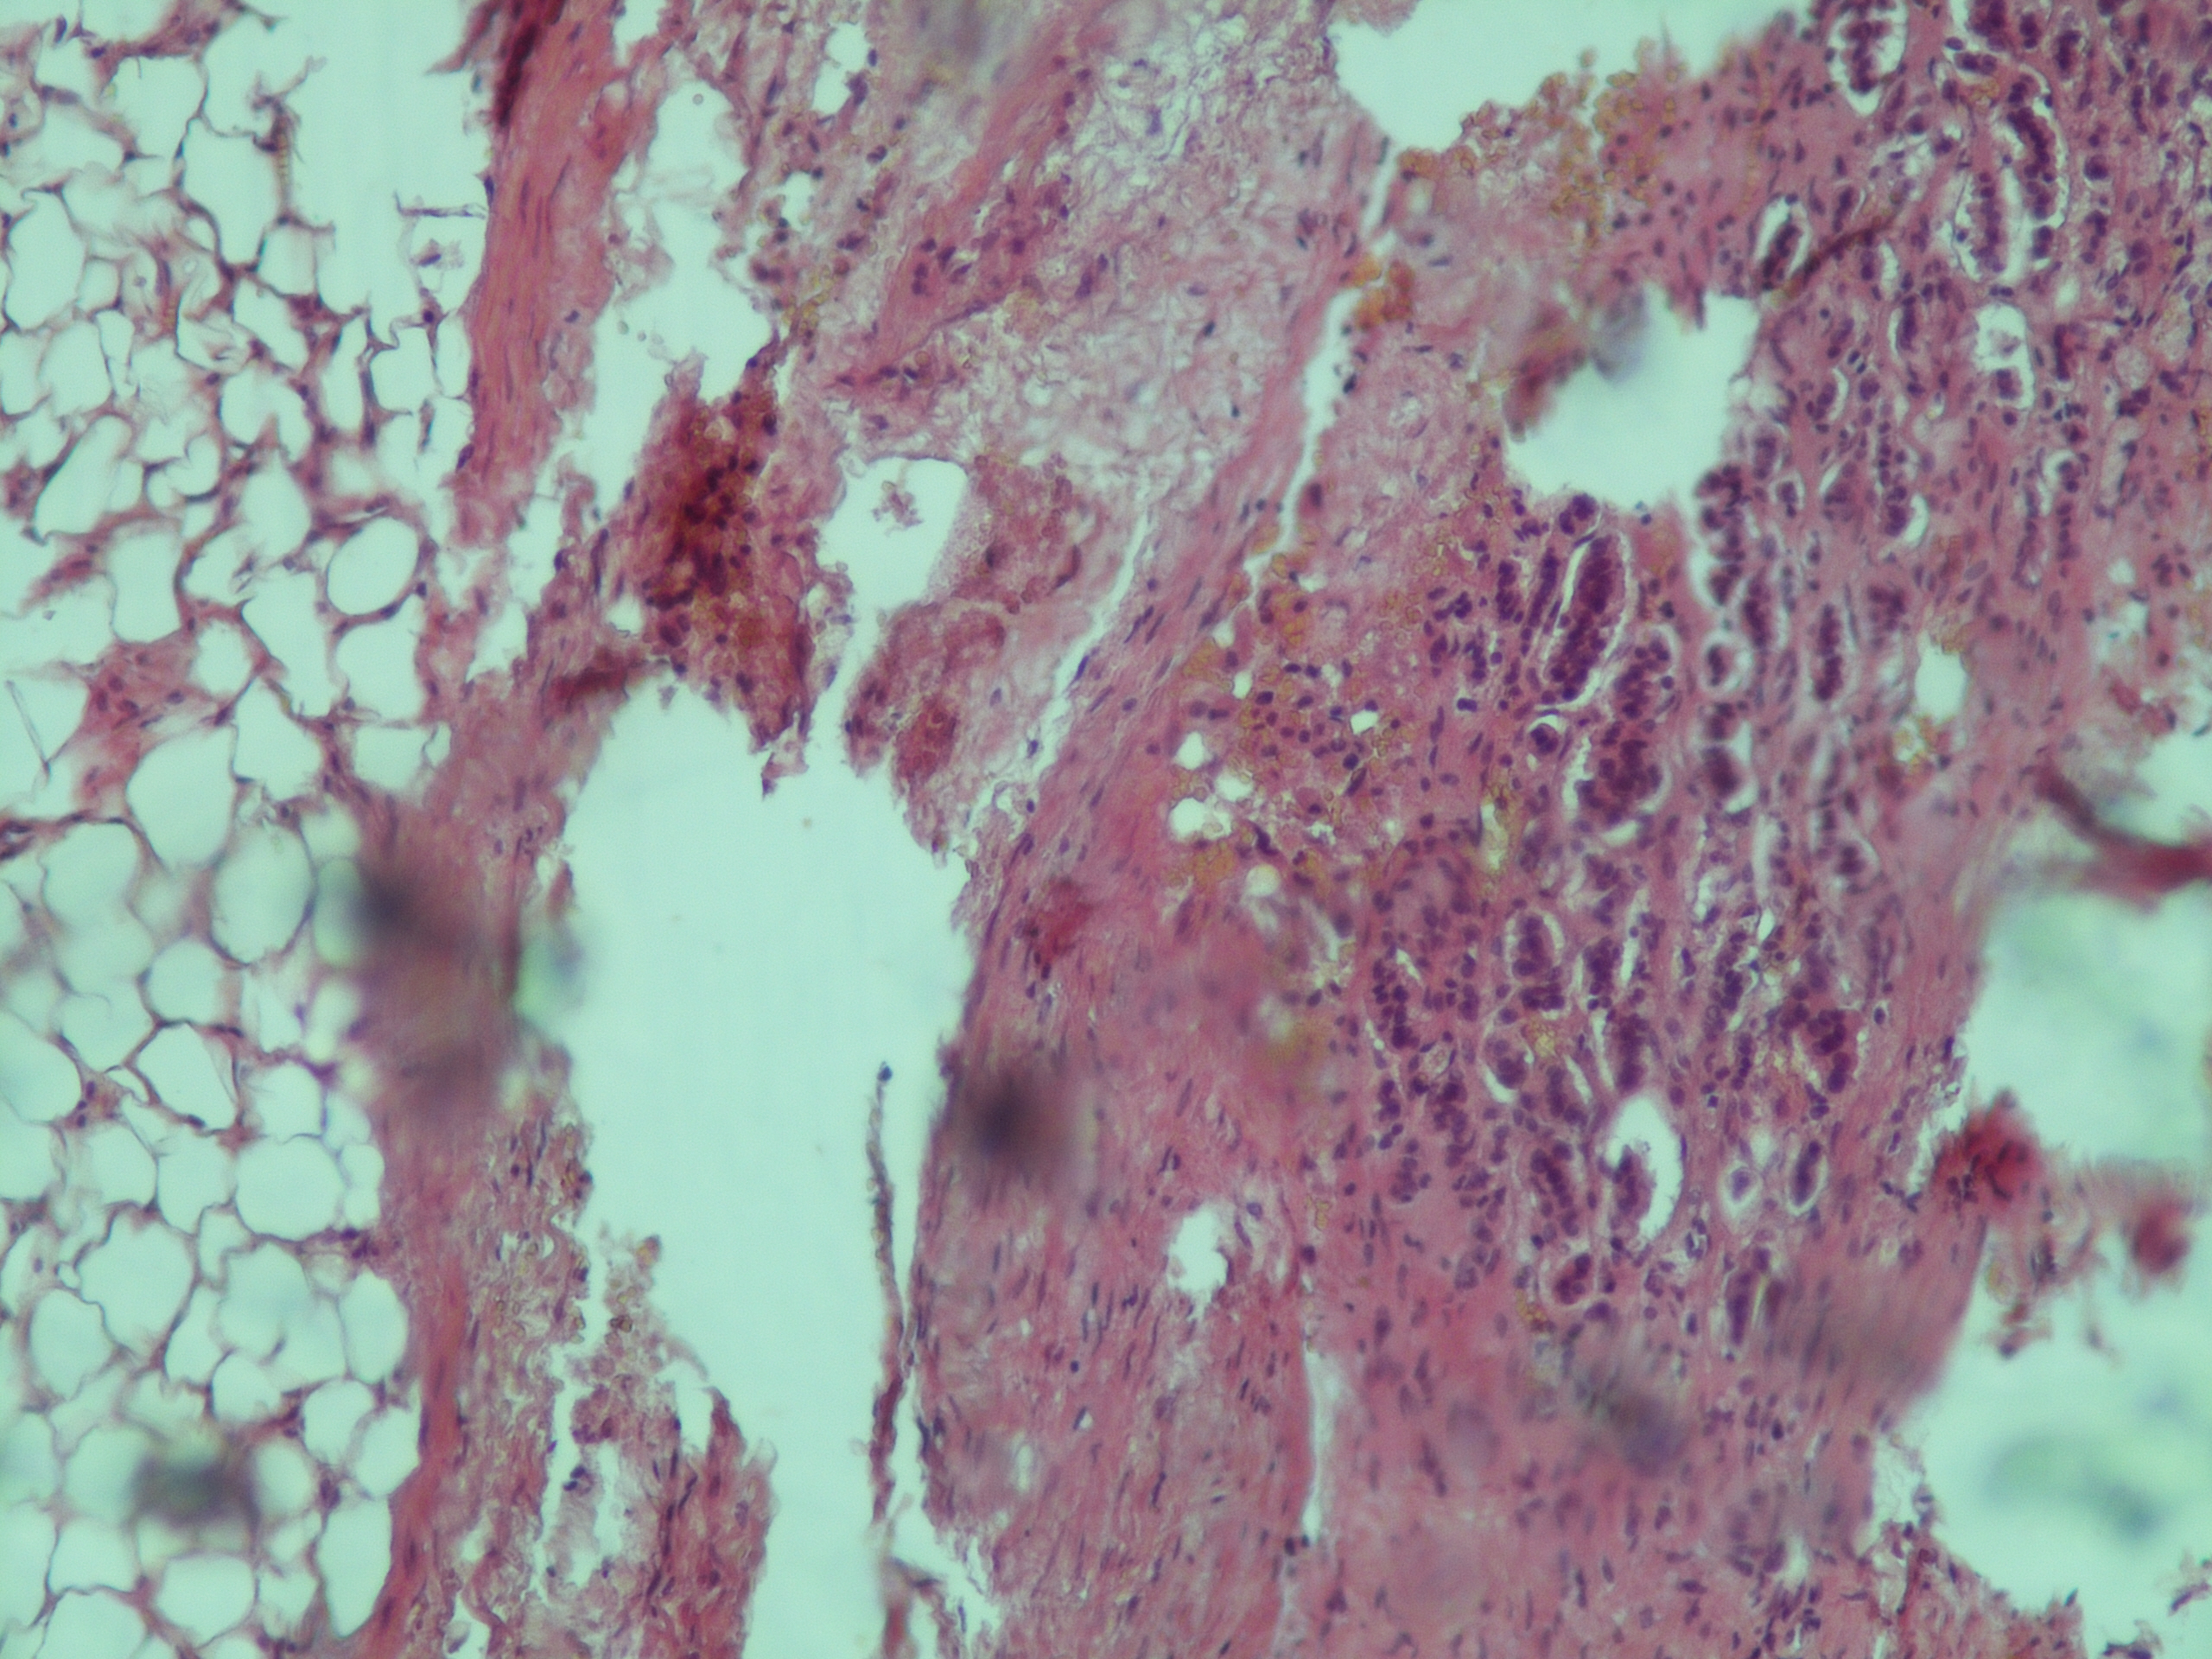

С целью определения гормональной активности образования был выполнен супрессивный тест с 1 мг дексаметазона: кортизол плазмы на следующее утро в 08:00 – 4,03 мкг/дл (норма <1,8 мкг/дл), АКТГ – 0,55 пмоль/л (1,6–13,9 пмоль/л), метанефрин в суточной моче – 373 мкг/сут (норма <320 мкг/сут), норметанефрин в суточной моче – 464 мкг/сут (норма <390 мкг/сут). Биохимические показатели: глюкоза крови натощак – 6,8 ммоль/л, общий холестерин – 4,9 ммоль/л. С учетом незначительного повышения в суточной моче уровня метанефрина и норметанефрина на фоне большого размера образования (41 × 42 × 56 мм) феохромоцитома была исключена. Пациент был направлен в ФГБУ РНИОИ с диагнозом “адренокортикальный рак, глюкокортикоид-продуцирующий”. Была выполнена лапароскопическая адреналэктомия слева. Заключение гистологического исследования удаленного образования: “Морфологическая картина более всего соответствует феохромоцитоме, дискомплексированный вариант, с очагами некроза, кровоизлияний, инвазия стенки сосудов (рис. 2, 3). Результат иммуногистохимического исследования: S-100 – отрицательная реакция, Сhromogranin A – умеренно выраженная цитоплазматическая реакция в клетках опухоли, Synaptophysin – слабо выраженная цитоплазматическая реакция в клетках опухоли, Ki-67 – позитивная ядерная реакция в единичных клетках опухоли. Заключение: морфологическая картина и иммунофенотип более всего соответствуют феохромоцитоме”.

Рис. 3. Гистологическая картина удаленного образца надпочечника (окраска гематоксилином и эозином, ×120). Феохромоцитома злокачественная с умеренным инвазивным ростом в кору надпочечника (слева направо), сосуды, некрозы и перивазарная воспалительная инфильтрация.

3. Рис. 3. Гистологическая картина удаленного образца надпочечника (окраска гематоксилином и эозином, ×120). Феохромоцитома злокачественная с умеренным инвазивным ростом в кору надпочечника (слева направо), сосуды, некрозы и перивазарная воспалительная инфильтрация. | |